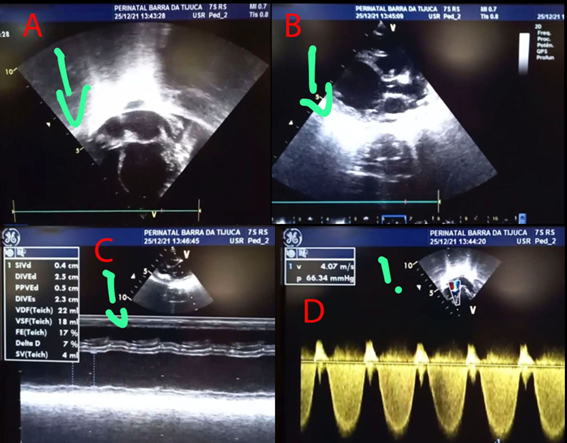

Isolated left ventricular non-compaction cardiomyopathy: case report and brief review on diagnostic imaging methods

José Victor da Nóbrega Borges, Samira Abdel Correia Leila, Manuella Guedes da Nóbrega Machado

73-77